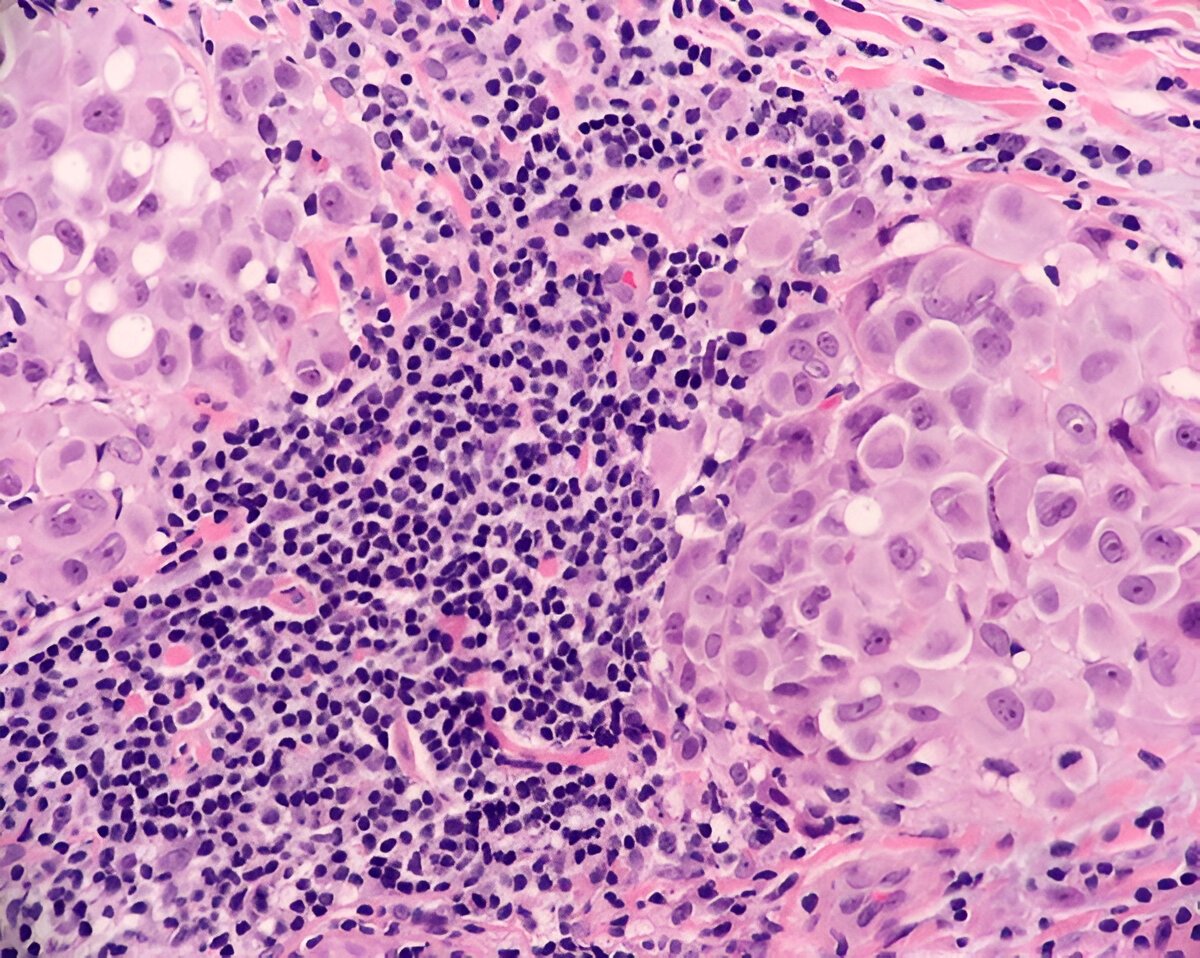

Основні способи — це біопсія та аналіз крові. Лікарі беруть зразок тканини та вивчають його під мікроскопом. Сподіваюся, ви розумієте, що це не виглядає як у популярних серіалах, де все виглядає надто спрощено. Тут потрібен справжній дар знаходити ці клітини серед багатьох інших.

Цей термін описує один із типів клітинної реакції організму. Коли організм зустрічається з проблемою – інфекція, травма чи щось інше, – наші імунні системи вирушають на бойові позу. Лімфоцити та гістіоцити прагнуть вторгнутися в уражені тканини, щоб вирішити проблему.

- Лімфоцити: Це білі кров’яні клітини, що відіграють роль солдат у нашій захисній системі.

- Гістіоцити: Їх ще називають макрофагами, і вони спеціалізуються на поїданні мікробів і утилізації мертвих клітин.